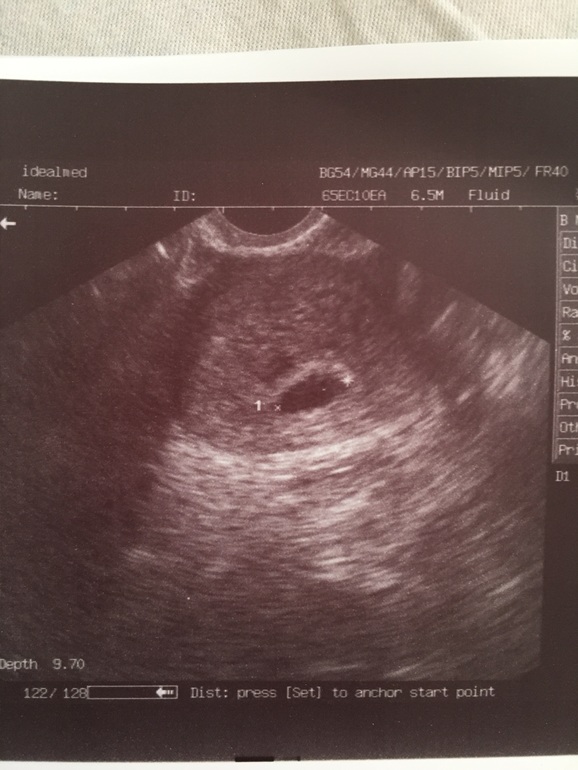

Сегодня 06.04 коричневая мазня чуть-чуть водичкой 😒 на УЗИ итог пя 16мм, желточный мешочек визуализируется, эмбриоши ещё нет. Ииииииии гематома ! Небольшая (на фото видно слева сверху над пя), а ведь ничего не болит, почему опять так...